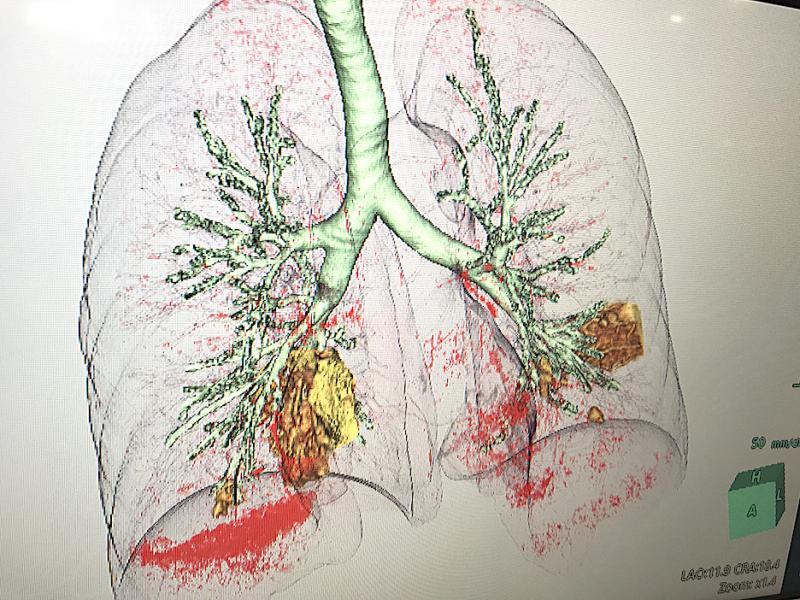

This photo gallery shows the variety of radiological presentations of COVID-19 (SARS-CoV-2) in medical imaging, including computed tomography (CT), radiograph X-rays, ultrasound, echocardiograms and magnetic resonance imaging (MRI). The radiology images show examples of typical COVID pneumonia in the lungs and the numerous complications the virus causes in the body in multiple organs, including the brain, kidneys, heart, abdomen and vascular system.

Ultrasound, especially hand-held ultrasound imaging devices, have become a primary imaging modality for novel coronavirus because of the ease to bag the device and sterilize it after use. CT and mobile X-ray systems are also used as front-line imaging systems for COVID-positive or suspected COVID patients.